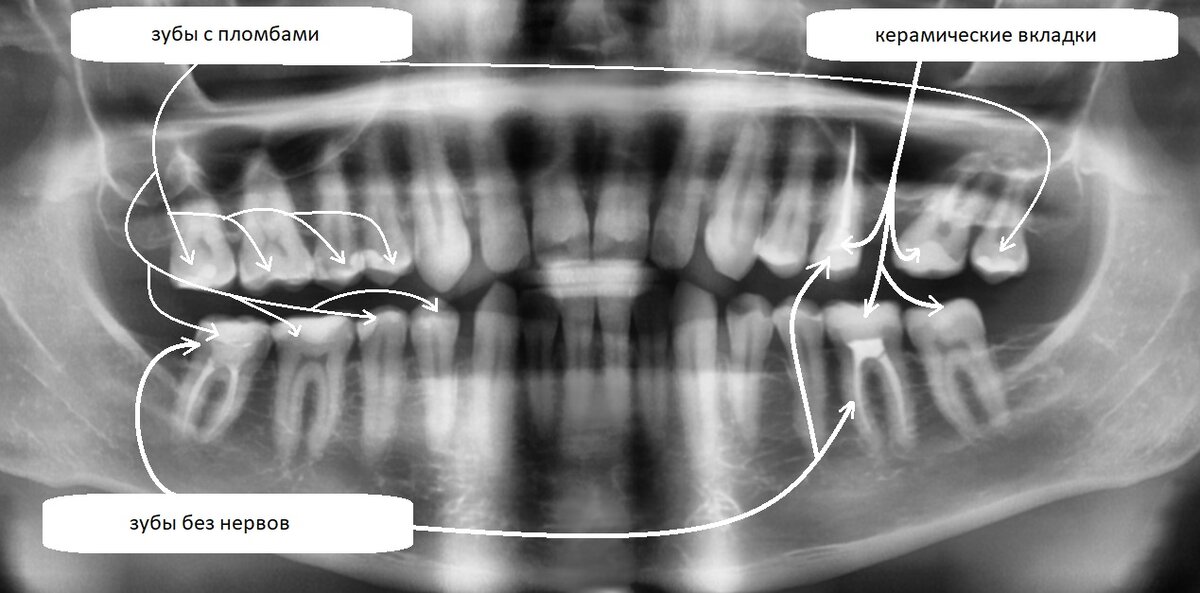

ортопантомограмма  от 5 декабря 2022 года

Выглядит вроде бы всё не так уж и плохо на первый взгляд. Видим что нет 1 зуба на верхней челюсти и костная ткань там убыла. Есть какие-то пломбочки, 3 зуба без нерва.

Итак, что на самом деле мы имеем? К 32 годам я уже бывалый стоматологический пациент.

У меня было 13 пломб (на всех жевательных и практически всех премолярах), затем я поменял 4 пломбы на 4 керамические вкладки на левой стороне. Есть 1 зуб мудрости слева сверху (остальных не было в зачатках). Да у меня только 1 зуб мудрости был и есть. И нет 1 зуба под номером 26 (его удалили около 13 лет назад).